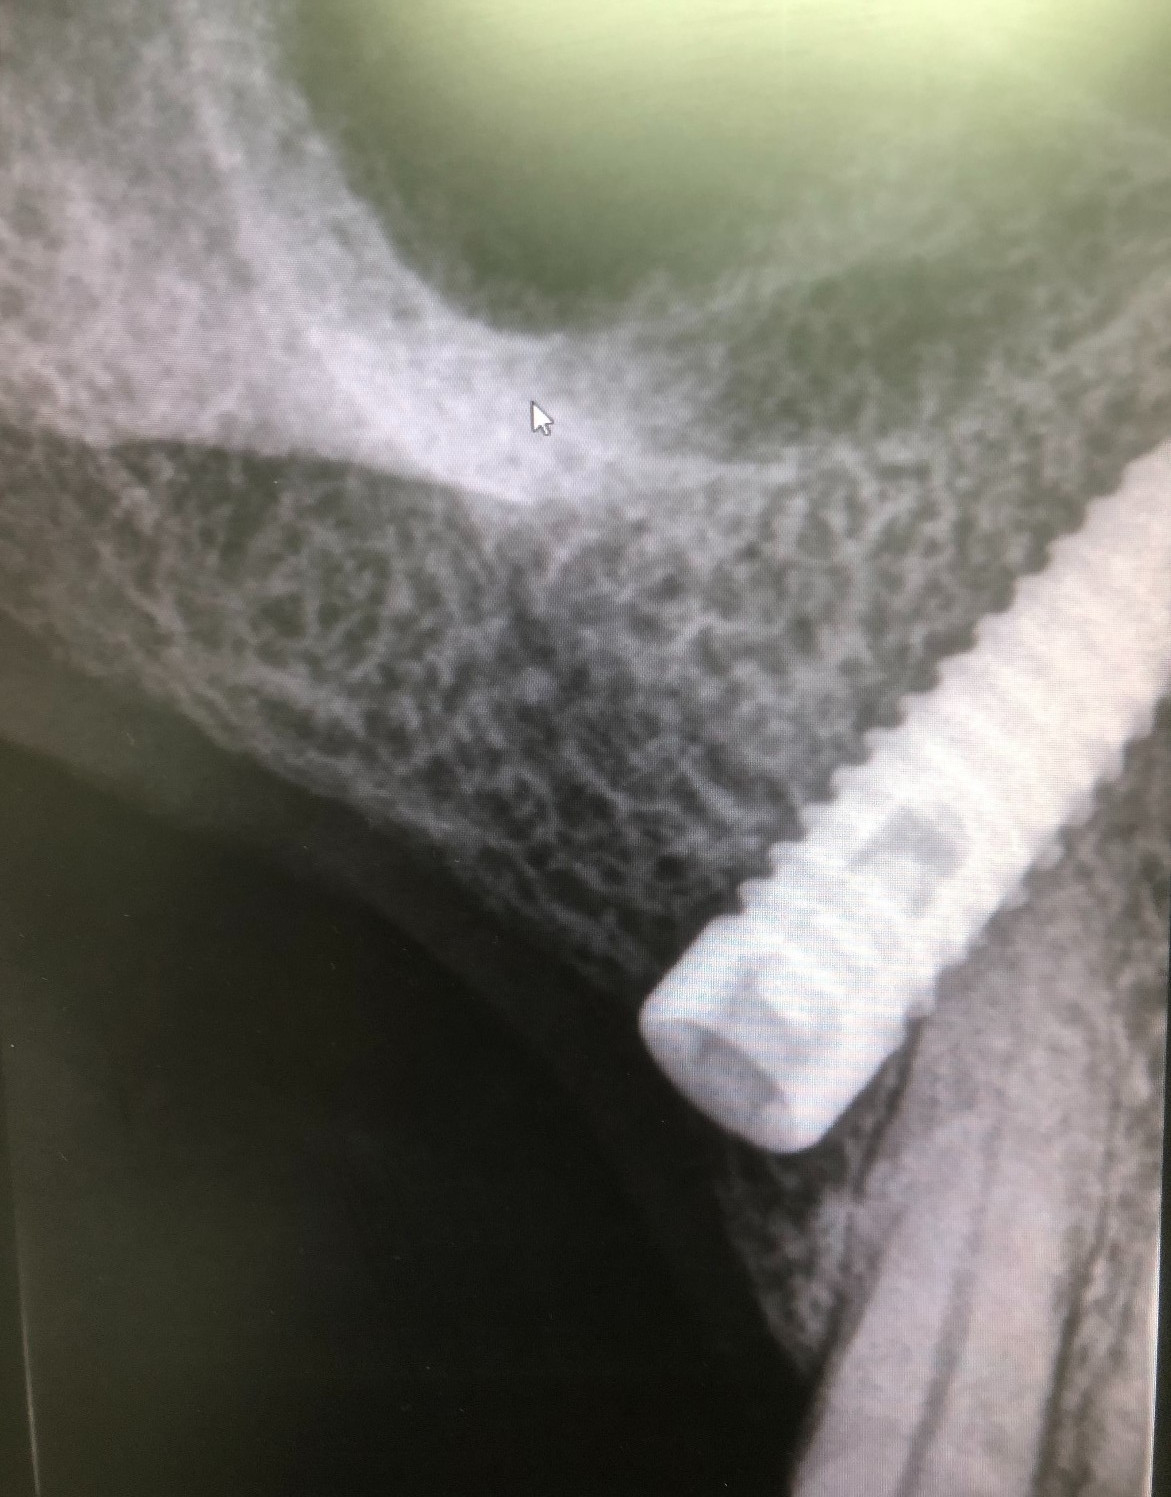

Debido a que la rosca no salió con la vibración optamos por rehacerla. Primero, procedemos al vaciado del implante con las fresas cañón estándar. Y continuación, realizamos el paso sucesivo de los machos de roscar por dentro del vaciado conseguido. Finalmente hemos rehecho la rosca.

Como hemos comentado es un molar, es decir, una pieza dental en la zona posterior de la boca y con una posición del implante muy inclinada para poder esquivar el seno maxilar, lo cual dificulta mucho el trabajo.